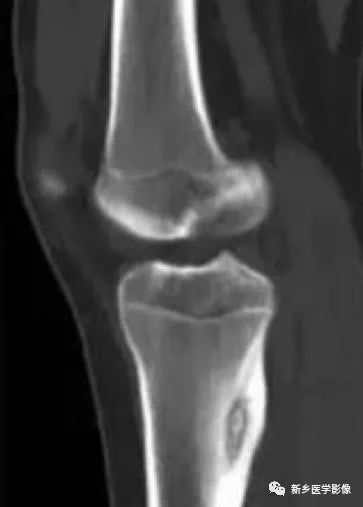

左股骨大转子骨样骨瘤1例X线CT

影像表现:

骨样骨瘤的影像学表现具有特征性,其典型的表现为:

瘤巢所在部位的骨质破坏及周围不同程度的骨质硬化,还可伴有骨膜反应、周围软组织或相邻关节的肿胀。

X线片上可分为皮质型,松质型和骨膜下型。

其中皮质型占70%,最常见,多见于长骨骨干。瘤巢靠近骨皮质内面,有小的透射线区域,周围是致密骨,若位于皮质内,则硬化环更明显。反应性增生硬化明显时,可遮盖瘤巢。

松质型:最常见于股骨颈,其次是手足的小骨和椎体,瘤巢位于骨端或不规则骨,周围硬化不明显,可仅有骨硬化边,病灶周围常无 新骨形成,但有密度增加的骨环包绕病灶。

骨膜下型:瘤巢位于骨皮质表面或骨膜下,肿瘤可侵蚀骨皮质形成浅凹状缺损,其表面形成数量不等的骨膜新生骨,通常骨附近的软组织肿块,最常见于股骨颈的内面及手和足。

CT/平片上,“瘤巢”周围多出现反应性骨质增生硬化:松质骨增生硬化或骨膜反应

骨样骨瘤是一种较常见的良性骨肿瘤,瘤巢的确定是影像诊断骨样骨瘤的关键:

平片仍然是诊断骨样骨瘤的重要手段;

CT是目前发现瘤巢的最佳方法;